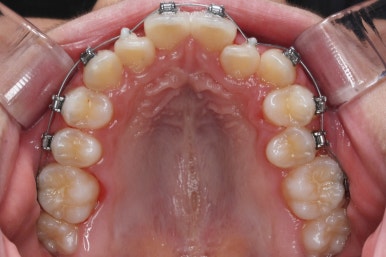

윗니들만 보게 되면 더 드라마틱한 것을 볼 수 있습니다.

악궁확장장치는 유지기간 이 후 다 제거가 되었고, 치아들이 매우 가지런해지는 것을 볼 수 있습니다.

이제 조금만 더 정리가 되면 장치 제거가 가능하겠네요.